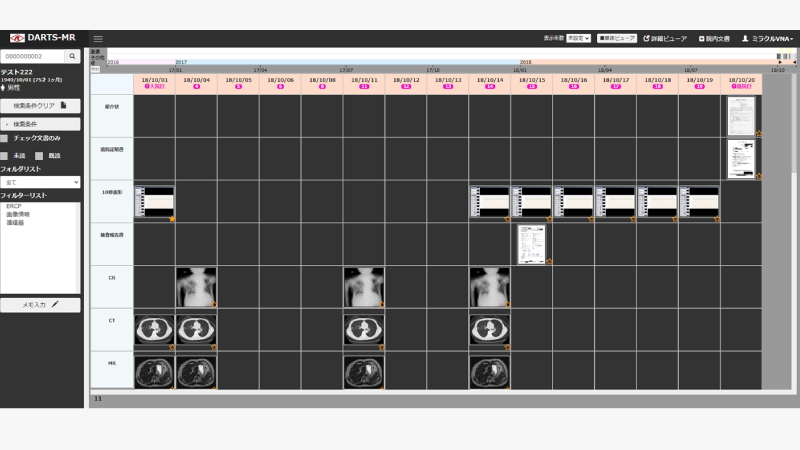

■統合Viewer M-DARTS

DICOMキー画像をはじめ、スキャン画像データやデジカメ画像データ等の非DICOM画像を一元管理・表示する統合Viewerです。

患者様単位で、登録情報をマトリックス上で直感的に表示します。